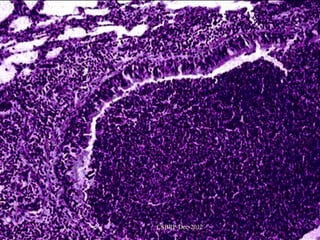

Dilatation of Bronchi & Bronchioles 2cms CSBRP-Dec-2012

A closer viewof the lung demonstrates the focal area of CSBRP-Dec-2012 dilated bronchi typical of bronchiectasis.

Fig15-3 Bronchiectasis in a patient with cystic fibrosis, who underwent lung transplantation. Cut surface of lung shows markedly distended peripheral bronchi filled with mucopurulent secretions. CSBRP-Dec-2012

Bronchiectasis is seenhere. The repeated episodes of inflammation can result in scarring, which has resulted in fibrous adhesions between the lobes. Fibrous pleural adhesions are common in persons who have had past episodes of inflammation of the lung that involve the pleura. With extensiveCSBRP-Dec-2012 the pleural space may be involvement, obliterated.